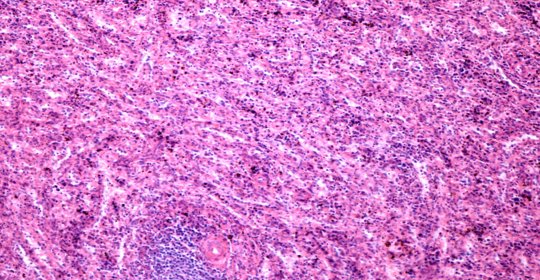

乳房囊腫:病因、診斷與治療

乳房囊腫:分類與處理

乳房腫塊:症狀、原因及診斷